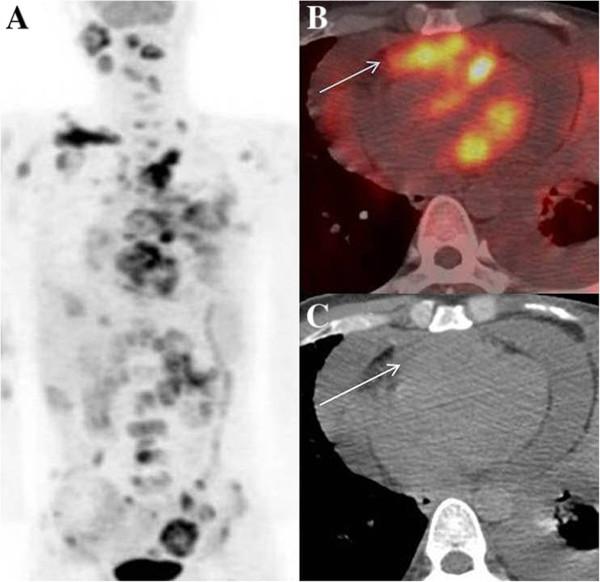

Metastatic involvement of the heart is a rare occurrence and remains undiagnosed until autopsy. In some instances, patients may have cardiac symptoms, leading to ante-mortem diagnosis. Although most primary cancers have been documented to metastasize to heart, the existing literature on cancers of upper aero-digestive tract is an exception, with only a few reports. We report four cases of upper aero-digestive tract cancers, three of which arise from oral cavity, one from lower esophagus, metastasising to the myocardium, detected on 18 F - Fluoro-deoxy-glucose Positron Emission Tomography/Computed Tomography (FDG PET/CT) study , in the absence of related symptoms.

心脏转移受累较为罕见,直至尸检时才得以诊断。在某些情况下,患者可能会出现心脏症状,从而得以生前诊断。尽管大多数原发性癌症都有转移至心脏的记录,但关于上消化道癌症的现有文献却是个例外,仅有少数报道。我们报告了4例上消化道癌症,其中3例起源于口腔,1例起源于食管下段,在没有相关症状的情况下,经18F-氟脱氧葡萄糖正电子发射断层扫描/计算机断层扫描(FDG PET/CT)检查发现转移至心肌。